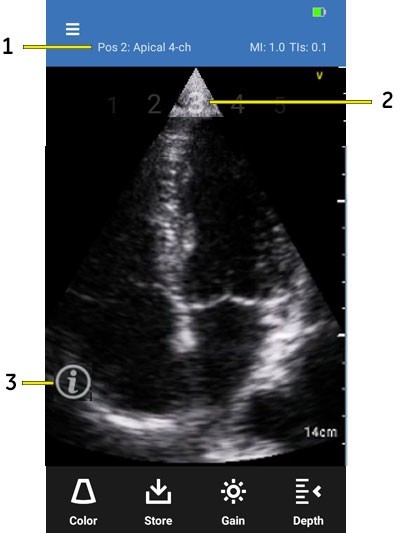

The live scan screen displays the following interface elements for the current protocol:

Interface elements

1. Current step name - displays the step text. For example, Parasternal Long - B mode

2. Step number - displays previous (for example 2), current (3) and next step numbers (4)

3. Info icon - invokes Scan Coach help windows for current step